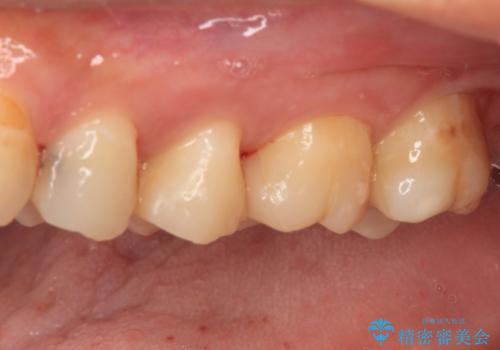

精度の高いセラミックインレーによる修復治療を行うこととしました。

処置を行った歯以外にもむし歯と思われる歯が多数ありますが、費用のかかる治療であれば、優先順位をつけて、処置を急ぐ歯から処置を進めて行きました。